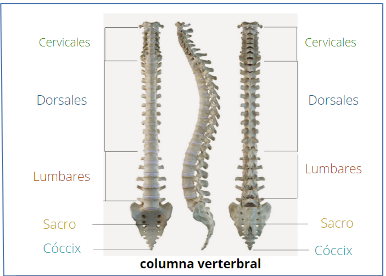

– Articular. En la osteopatía articular tratamos el aparato músculo – esquelético, donde vemos problemas relacionados de cervicales, dorsales, lumbares, sacro y cóccix.